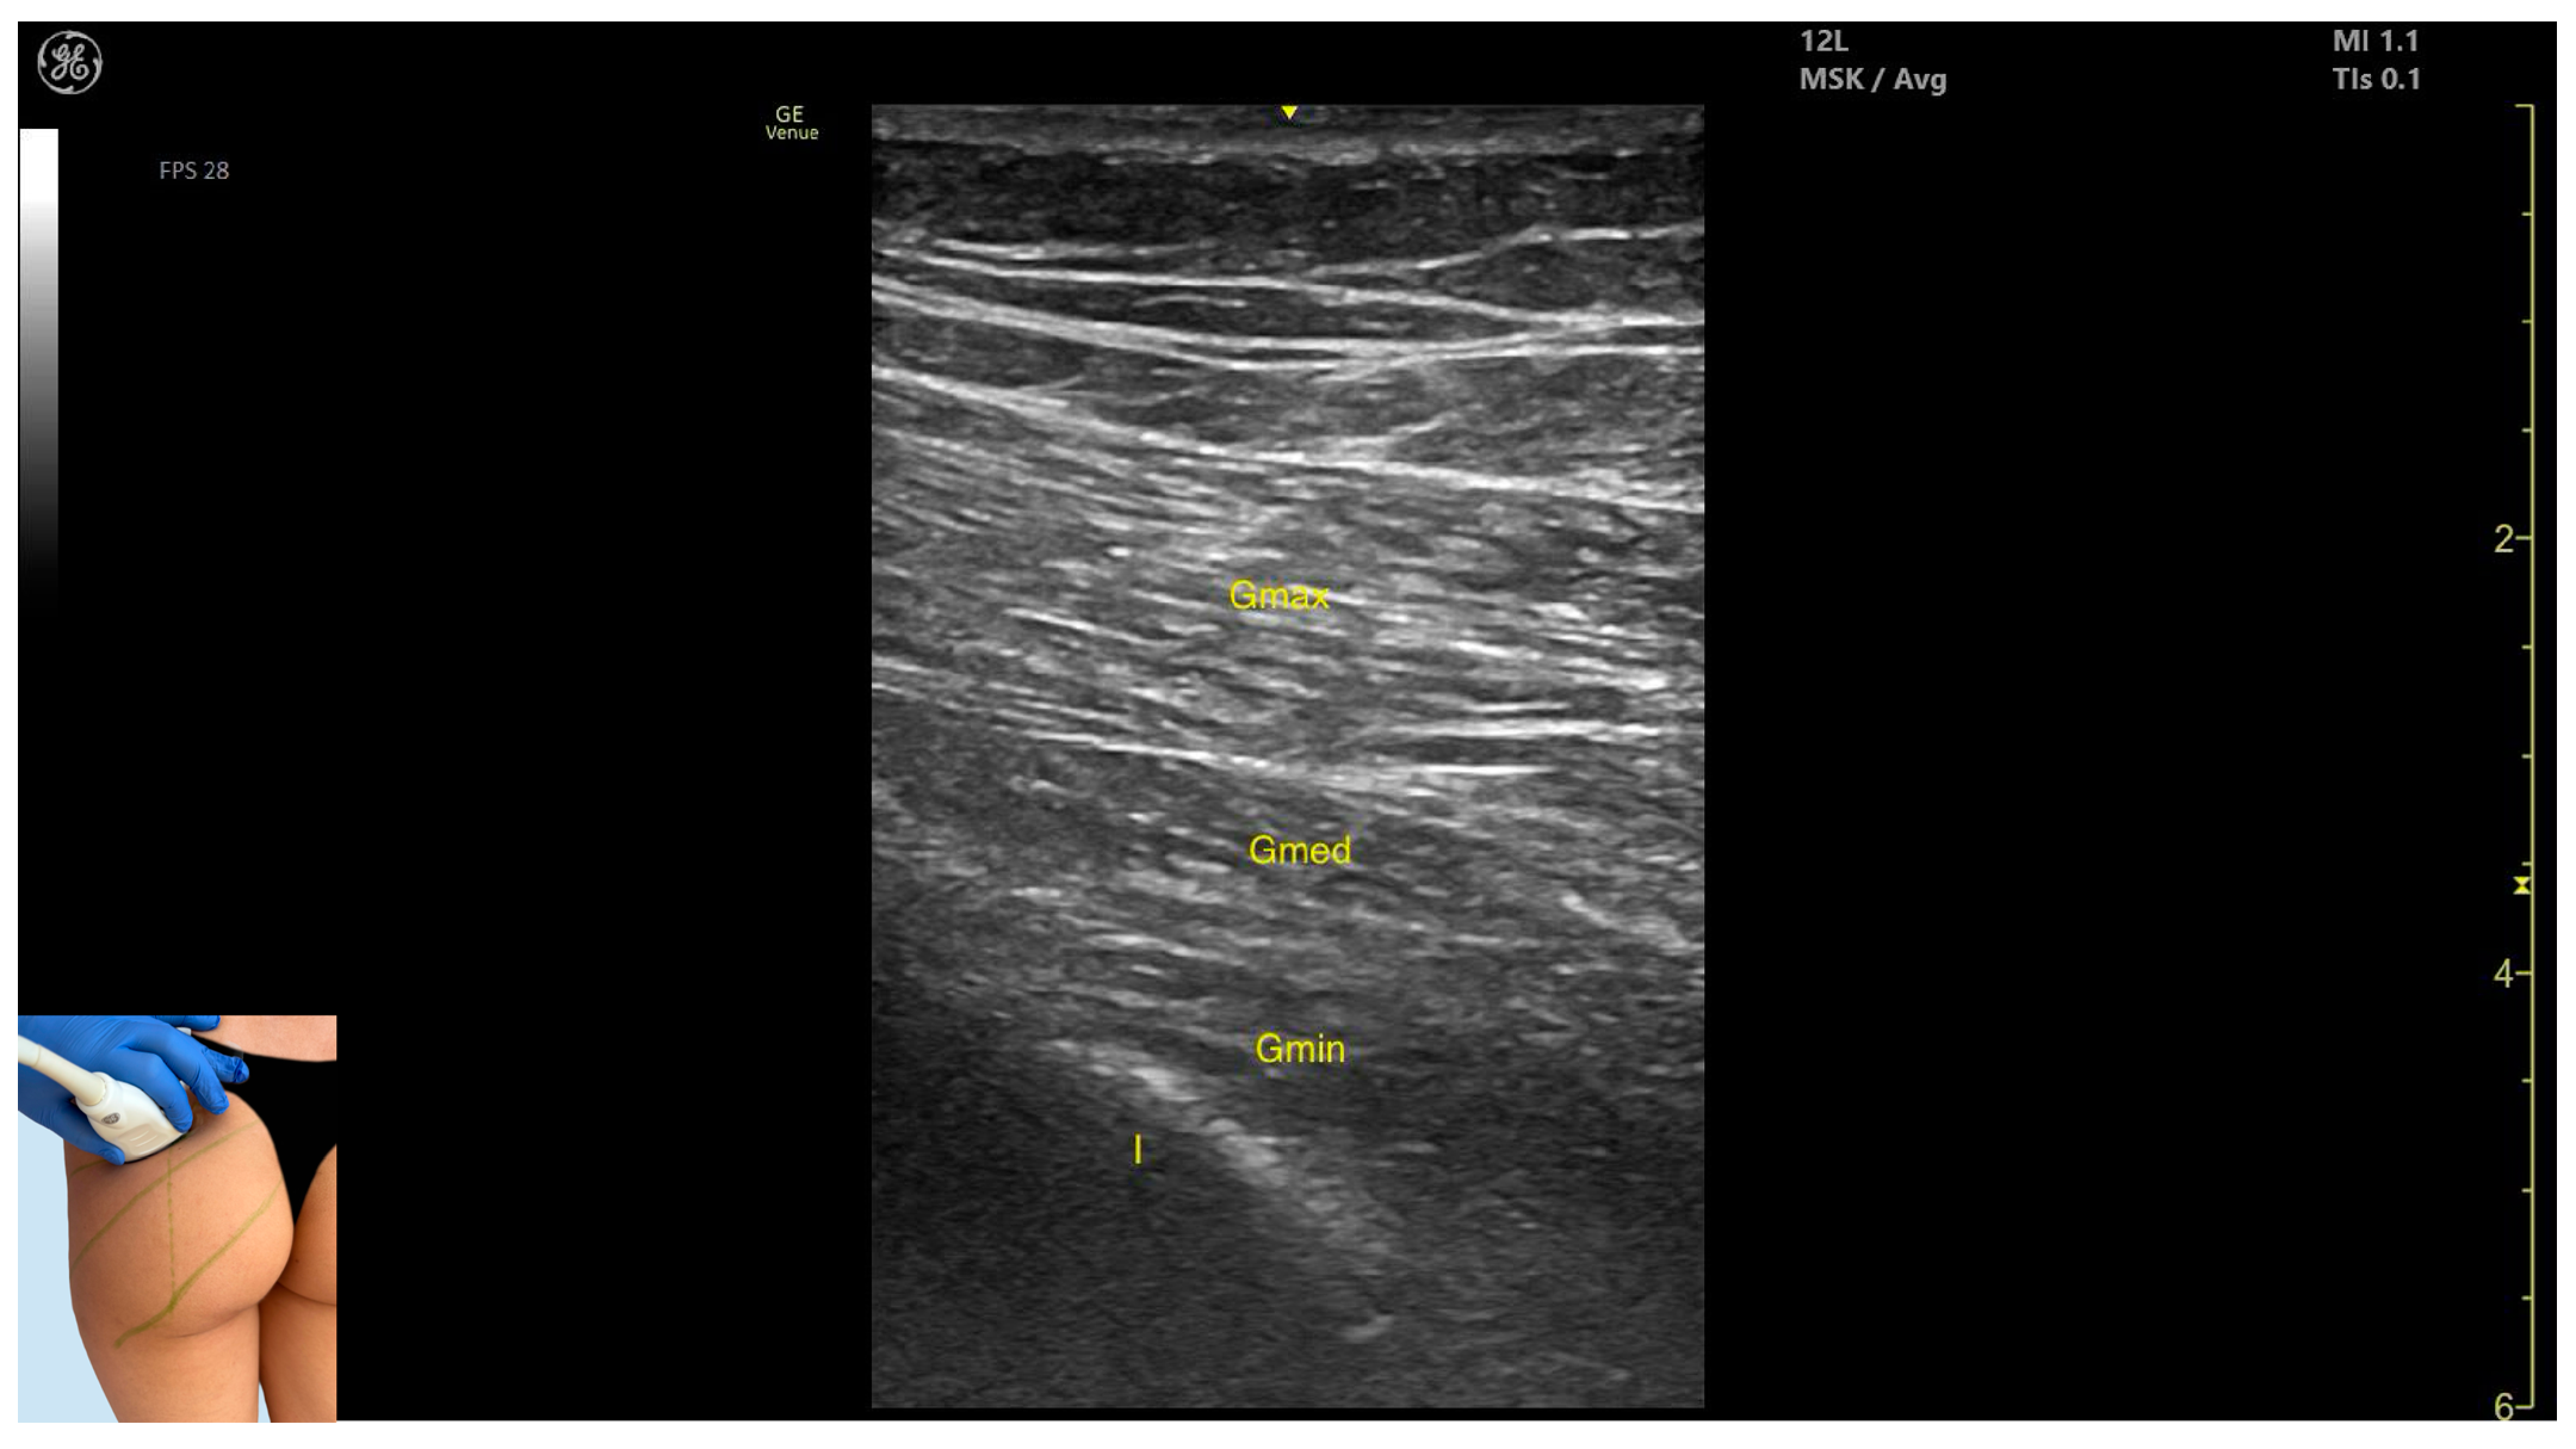

3.1. Gluteus Maximus (Gmax)

3.1.2. Ultrasound Identification

3.1.3. Key Ultrasound Landmarks

- Muscle morphology: It is the strongest and most superficial muscle in the gluteal group.

- Muscle position: It represents the most superficial muscle mass at this level. It lies superficial to both the gluteus medius and gluteus minimus.

- External fascia: It is enclosed by a pronounced fascia, which separates it from the subcutaneous tissue and the gluteus medius, facilitating botulinum toxin injection.

- Dynamic evaluation: During dynamic evaluation, scanning laterally toward the hip joint reveals an increase in muscle thickness of the gluteus medius and gluteus minimus. Muscle contraction is visible during hip extension and external rotation maneuvers.